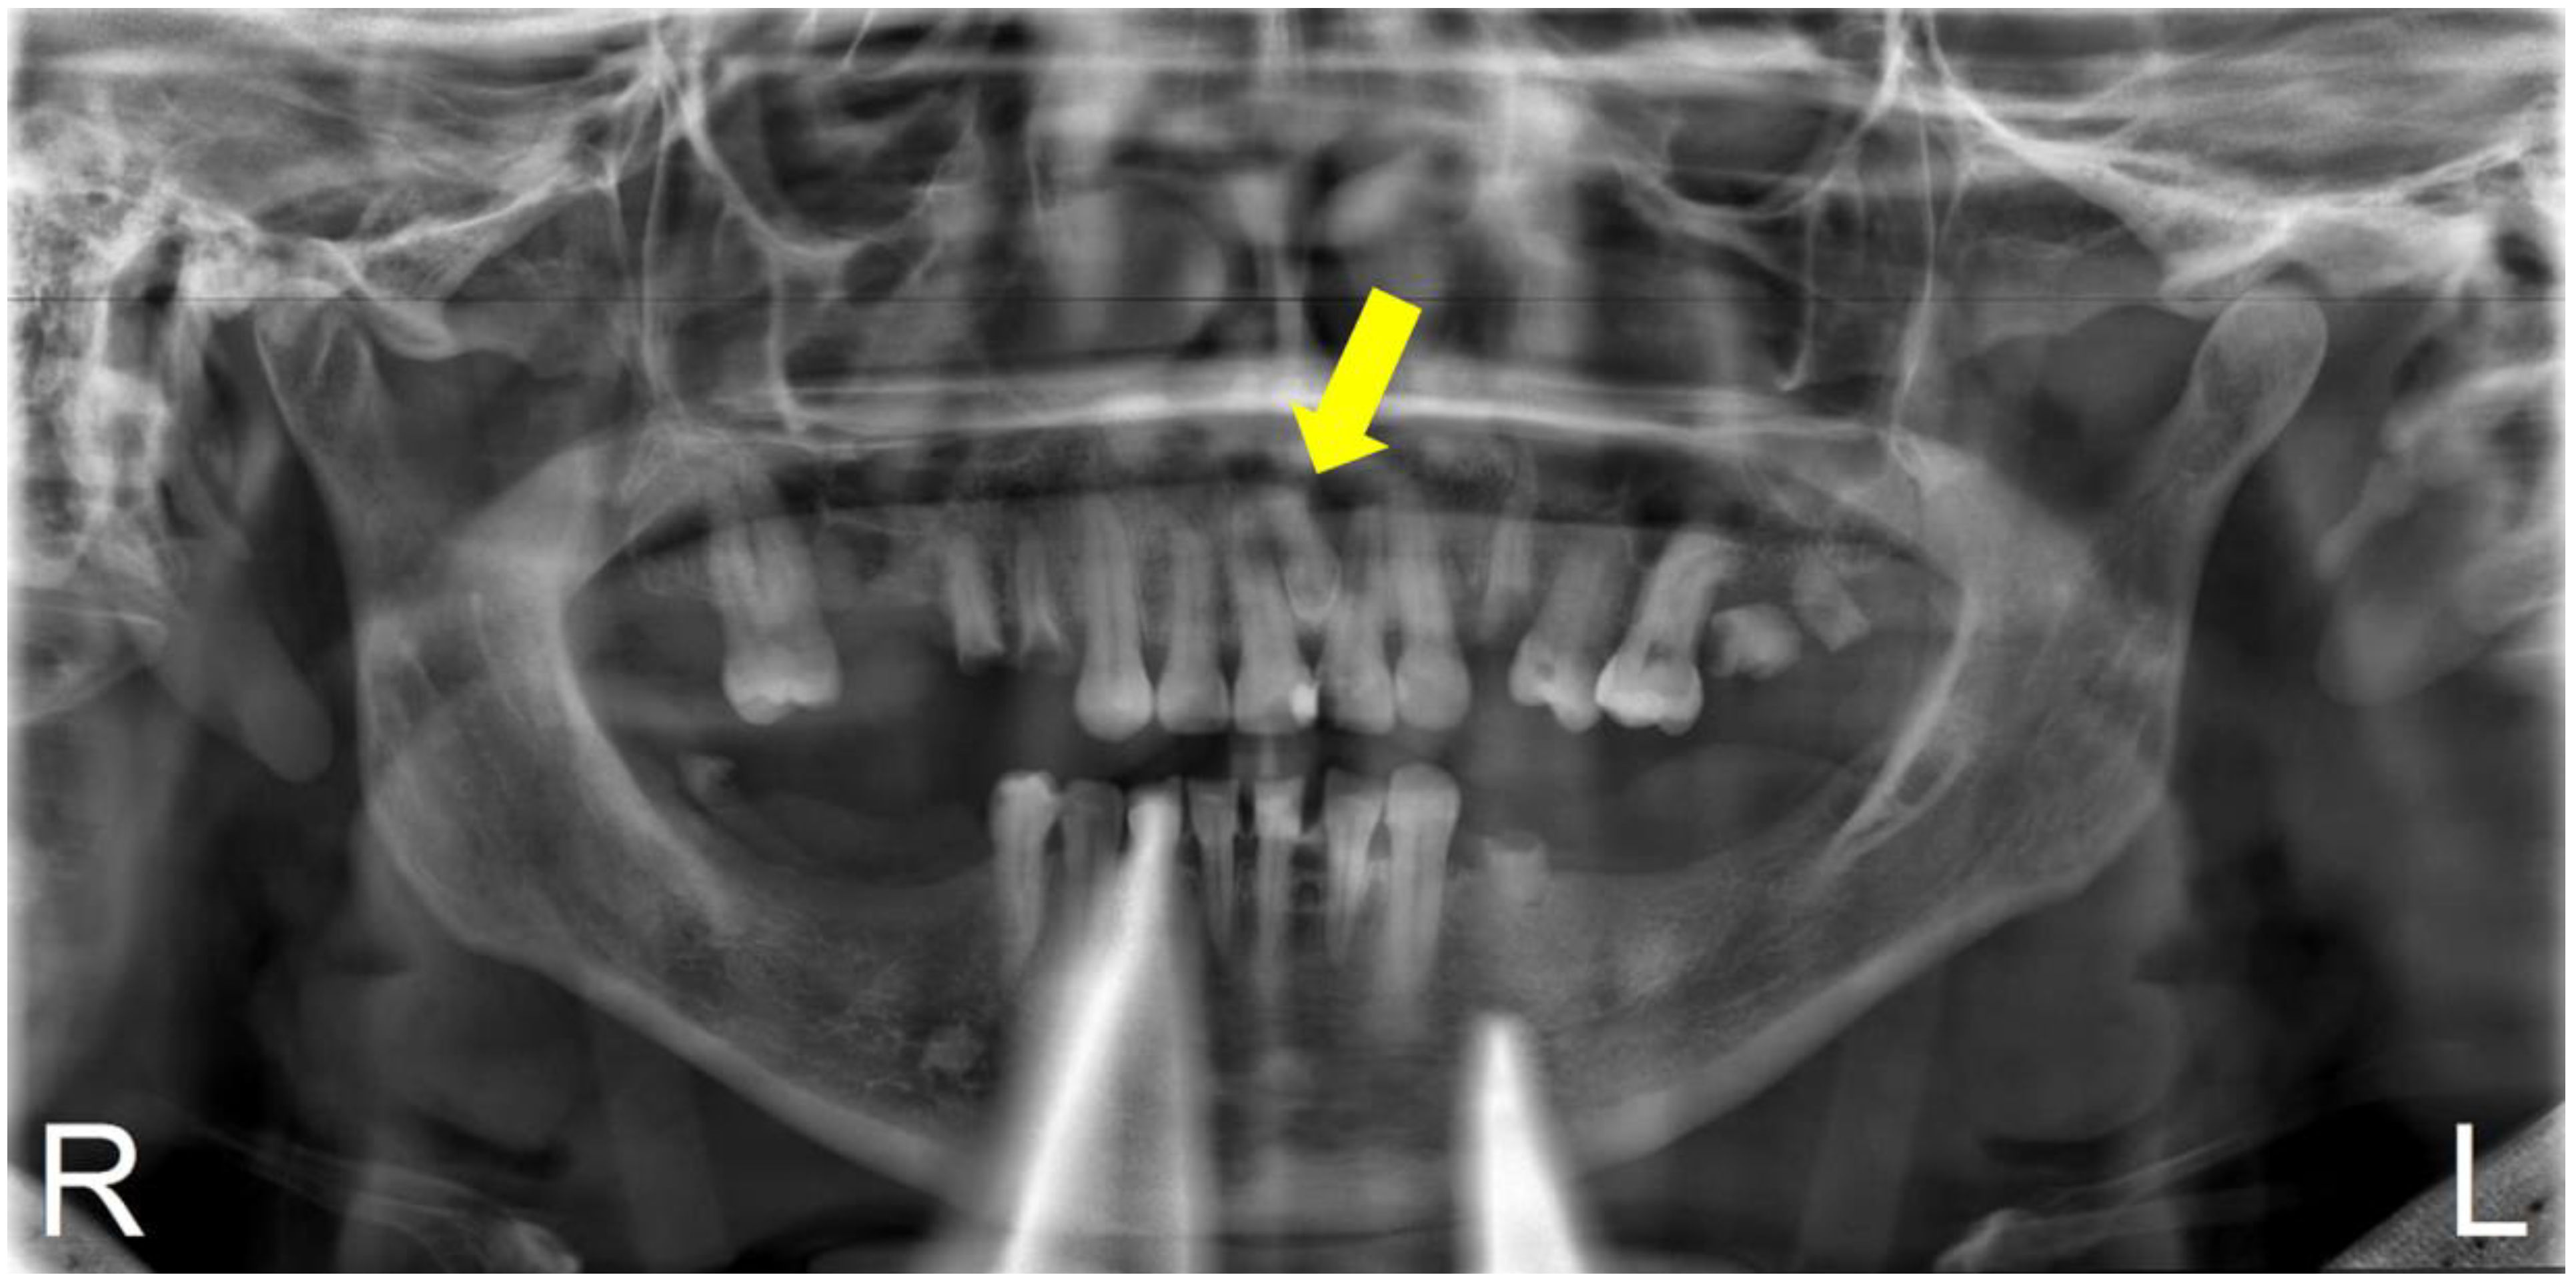

2.1. Case Report 1

| Case Report 1 | Male | Conoid mesiodens with dilaceration in close contact to tooth 2.1, horizontal position | 9 years old | Clinically, due to increased palatal volume | Tooth vestibuloversion 2.1 Palatal volume increase |